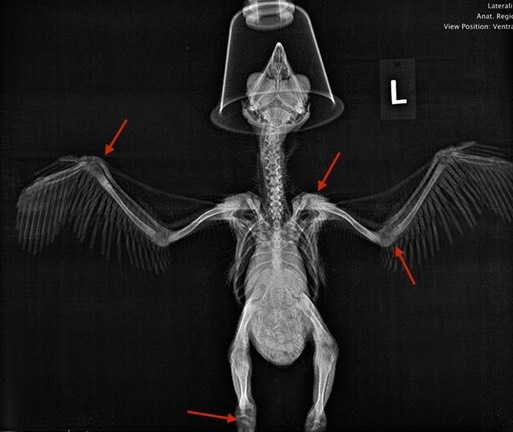

Five more nestling Great Horned Owls were admitted this past week. One had multiple injuries, but the prognosis for a full recovery is good.

The broken wing of the nestling Great Horned Owl admitted last week has healed nicely.